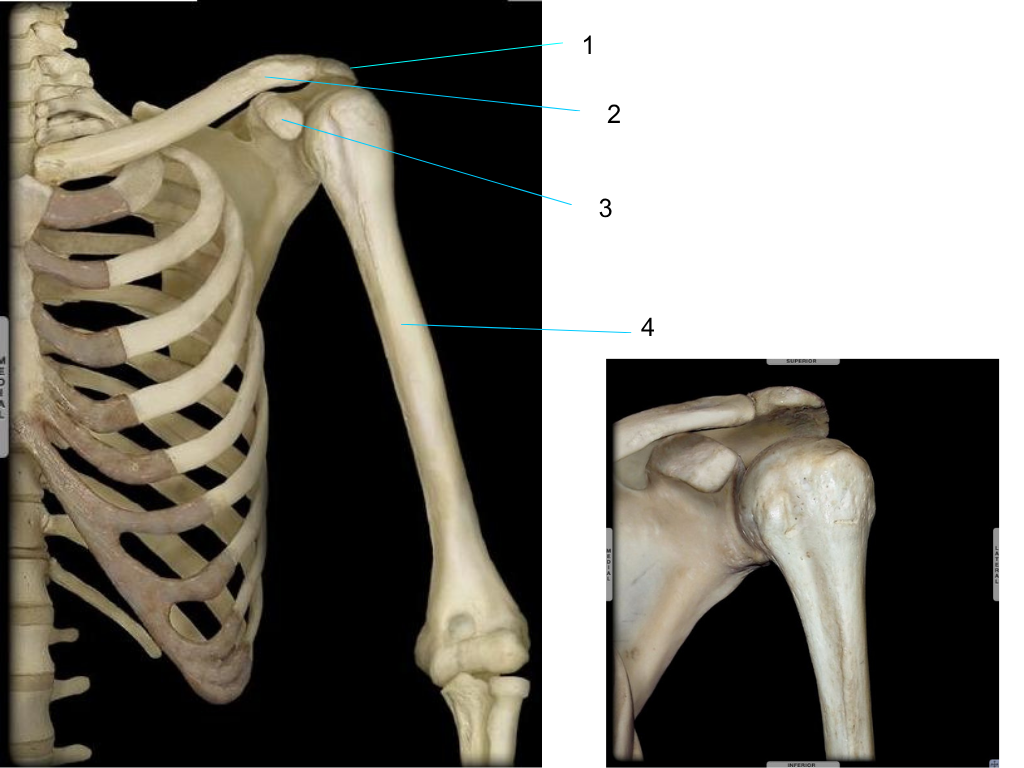

scapula

what is #1 pointing at?

spine

what is #2 pointing at?

acromion

what is #3 pointing at?

glenoid fossa

what is #4 pointing at?

acromion of scapula

clavicle

coracoid process of scapula

humerus